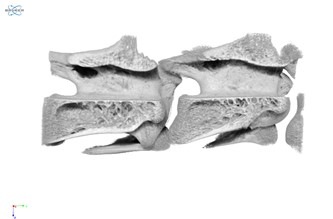

Figure 5: Clipped volumetric rendering of chicken vertebrae showing fine trabecular bone structures

A closer inspection within the vertebrae reveals the fine trabecular structure within the bones, as shown in Figure 5.